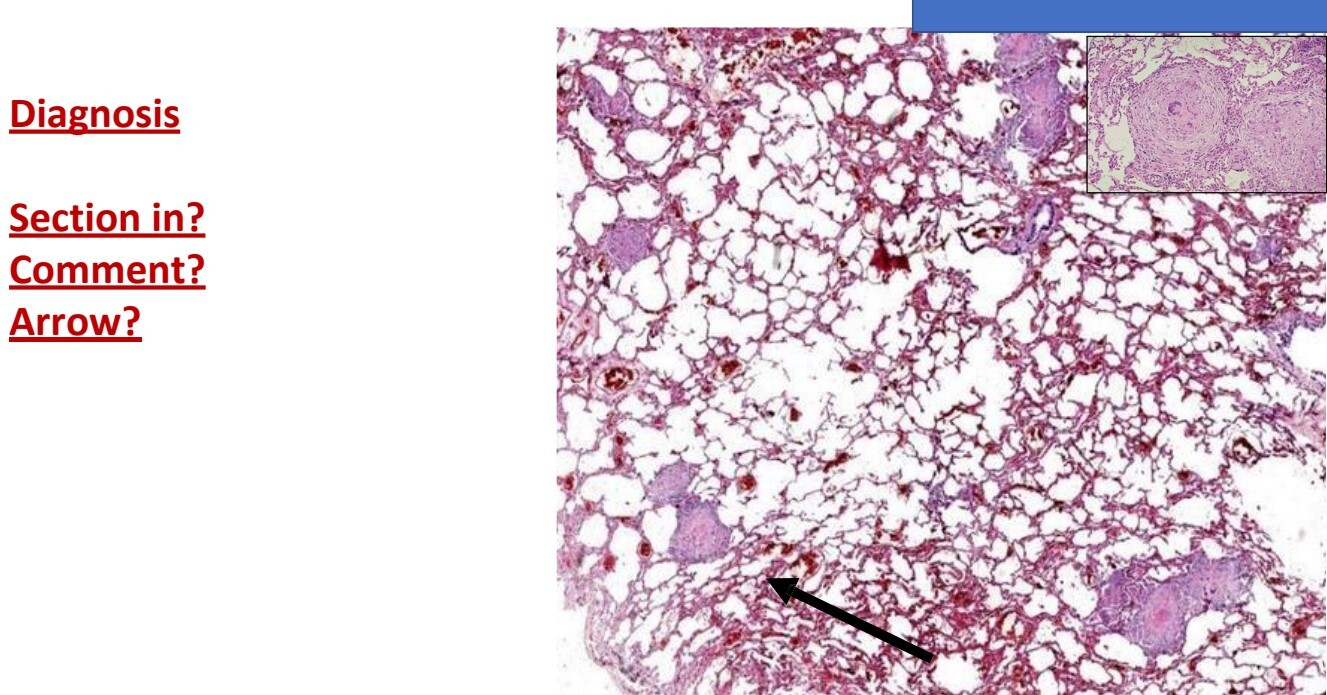

Chronic venous congestion in lung

Lung section

Alveolar wall are thickened due to interstitial edema and congested

Alveolar spaces contain transudate, entangling red cells and hemosiderin granules (the BROWN CELL)